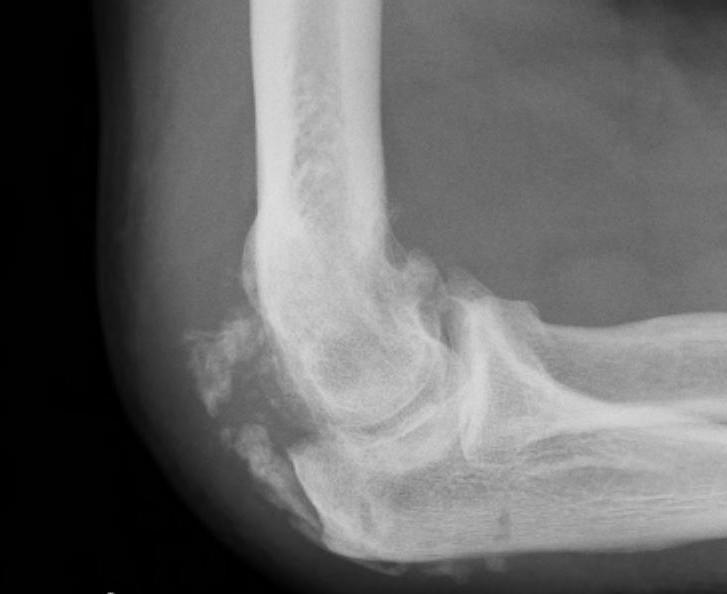

Xray

Radio-ulna synostosis

Mature bone

- smooth well demarcated edges on xray